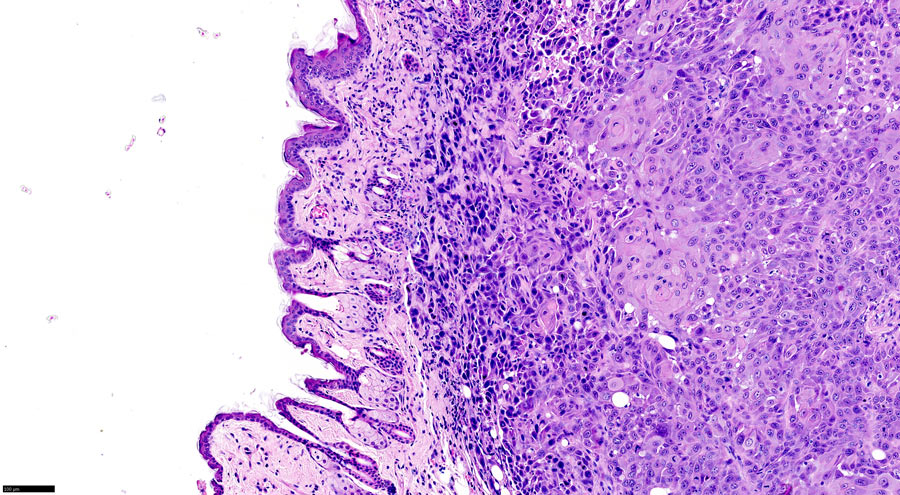

寻找肿瘤生物标志物可以帮助在早期阶段诊断口腔癌。

在口腔肿瘤组织中,几乎90%携带线粒体突变。

口腔癌中的线粒体突变

口腔癌是世界上第六次常见的癌症。在高级阶段检测到大多数口腔癌,这对患者护理和治疗不理想。寻找肿瘤生物标志物可以帮助在早期阶段诊断口腔癌症。考虑到这一点,Mbaye博士在45个口腔癌中检查了线粒体基因组的MT-CYB和D环序列:分析了来自对照和肿瘤组织的线粒体DNA的D圈和MT-CYB区域,任何DNA序列差异被认为是体细胞突变。

在口腔肿瘤组织中,几乎90%携带线粒体突变。在D圈区域中突变比中的突变更频繁MT-Cyb.基因:观察到的突变的近80%在D环区域,而仅20%影响了MT-Cyb.基因。这并不一定意味着在D圈区域中自然发生的突变比在MT-Cyb.基因,但表明D环区域中的突变更可能具有严重的后果和有利于在线粒体基因组的其他部分发生的突变。